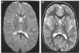

Pantothenate kinase-associated neurodegeneration (PKAN), formerly called Hallervorden–Spatz syndrome, is a genetic degenerative disease of the brain that can lead to parkinsonism, dystonia, dementia, and ultimately death. Neurodegeneration in PKAN is accompanied by an excess of iron that progressively builds up in the brain. [Source: Wikipedia